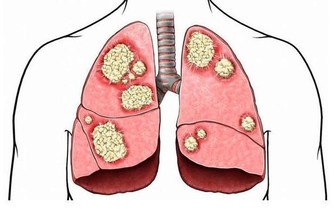

導致機體免疫機能下降、代謝障礙、營養失衡、勞損等問題的出現,所以變老是一種病理過程。

是由於變老的生理變化和病理變化,使患病的機率升高,衰老本身就是許多疾病的風險因素。

所以,變老不僅包括機體生理上的衰退,也包括在這個過程中發生的病理變化。